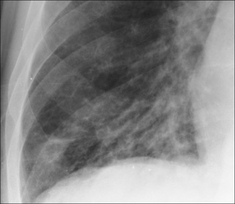

Figure 30.11 Mild haemoptysis due to bronchiectasis. The crowding of vessels and the prominent tramlines (thickened bronchial walls) at the right base raised the suggestion of bronchiectasis. Bronchiectasis was subsequently confirmed on CT.